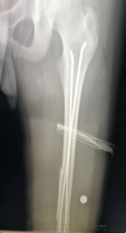

?? 十歲的小星(化名)不小心摔了一跤,當(dāng)時(shí)就感覺(jué)到腿部陣陣劇烈的疼痛。父母帶著他來(lái)到我院骨傷一科就診,經(jīng)過(guò)相關(guān)詳細(xì)檢查后確診為股骨干骨折,需要?jiǎng)邮中g(shù)治療。孩子這么小就要開(kāi)刀動(dòng)手術(shù)?手術(shù)會(huì)不會(huì)有危險(xiǎn)?手術(shù)后能不能痊愈?這一系列的擔(dān)心急壞了小星的父母……?別怕:手術(shù)只打一個(gè)小孔!“我院最新的彈性髓內(nèi)釘...